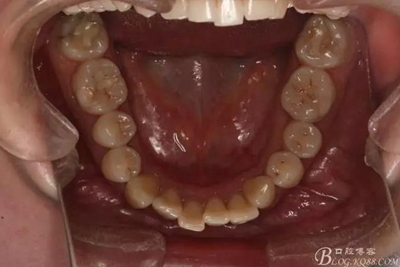

該病例主要為17、27頰側(cè)位同時(shí)伴有伸長(zhǎng),當(dāng)然種植支抗可以解決,但還有簡(jiǎn)單實(shí)用的辦法嗎?如圖,在橫腭桿遠(yuǎn)中延伸出牽引鉤,位置盡量遠(yuǎn)離合平面,7粘舌側(cè)扣,牽引力的方向?yàn)閴旱图吧嘞?,下圖為兩個(gè)月的效果,17已到位,27還未到位。